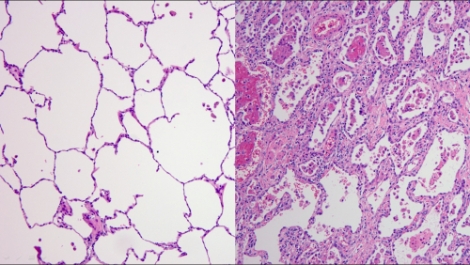

하지만 환자는 바이러스만 사라졌을 뿐 폐 상태는 나빠졌다. 흉부X-ray 검사 결과에서는 심한 특이사항이 발견되지 않았지만, 흉부CT 검사 결과 양측 폐에 광범위한 침윤소견과 폐섬유화 속도가 상당히 빨랐다. 폐 기능이 너무 심하게 손상돼 에크모를 떼는 순간 환자는 사망 위험이 높았다. 선택은 폐이식 밖에 없었고 의료진은 폐이식을 결정했다.

에크모센터장 흉부외과 김형수 교수는 “코로나19 환자 중 국내에서 최고의 중증치료 사례였으며 코로나바이러스에 감염된 폐를 떼어낼 때 건강한 폐와 다르게 크기도 작게 수축 되었고 마치 돌덩이처럼 폐가 딱딱한 느낌이었다”며 “건강하고 젊은 코로나19 감염증 환자도 폐섬유화 진행 속도가 빨라 폐이식까지 갈 수 있으니 젊다고 방심하지 말고 감염을 막기 위한 사회적 거리두기, 마스크 착용 등의 노력을 지속해야 한다”고 강조했다.

에크모센터 호흡기내과 박성훈 교수는 “코로나19 환자의 특징은 영상검사에서는 잘 나타나지 않았지만 실제로 폐섬유화 진행속도가 빨라 자칫 놓칠 수도 있어 환자 관찰이 중요하다”며 “현재까지 환자가 급성거부반응을 나타나지는 않았다. 이를 유지하기 위해 다학제 진료를 통해 환자의 건강상태를 면밀하게 파악하고 급성거부반응의 위험성을 낮추기 위해 면역억제제 농도를 조절하고 재활운동에 집중하고 있다”고 설명했다.